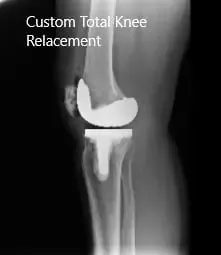

Post-Operative X-ray images showing AP and Lateral view:

The patient underwent a custom left total knee replacement with iTotal tibial tray with iTotal femoral implant with iTotal poly 32 mm patella with a 6-mm polyethylene insert.

The patient had an excellent recovery post arthroplasty. Her surgical wound was clean, dry and intact. The patient underwent an extensive program of physical therapy and a home exercise program.

During subsequent visits, she demonstrated a full range of motion with no pain. She stated she is now able to carry her daily activities without pain. She has since returned to work stating that she feels more motivated towards her work.